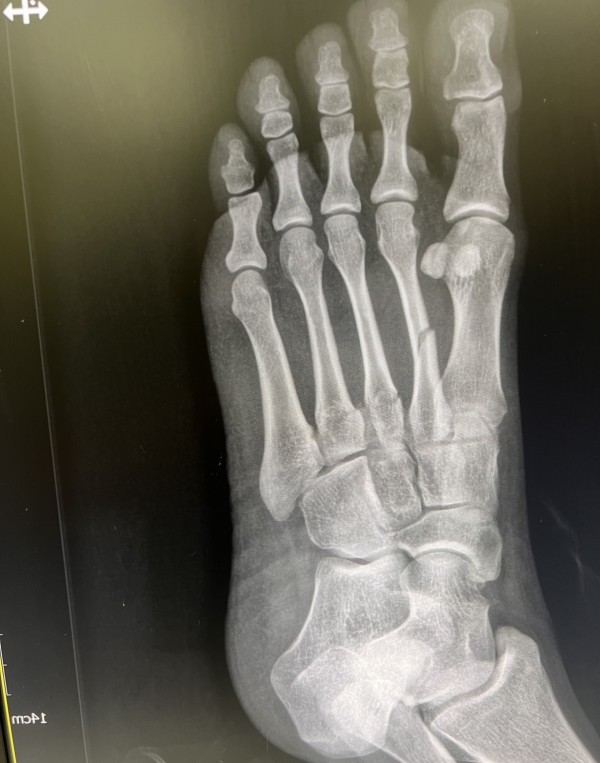

김지범원장 중족골골절

올렸는데, 안떠서 같은사진두장,, 사진재첨부해드립니다! 감사합니다

안녕하세요 두발로 병원 김지범입니다.

상기 골절은 2-3-4 중족골이 연달아 부러진거라, 지지력이 약할수 있어 저는 수술을 권합니다.